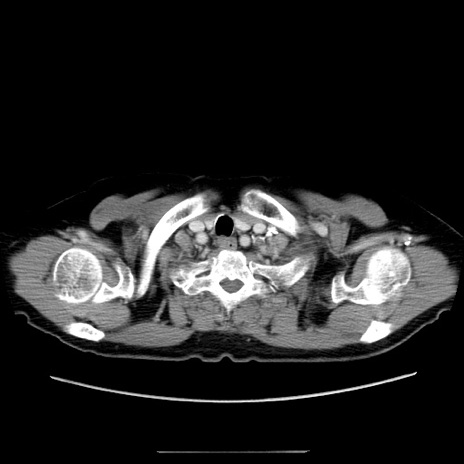

症例5(横断像)

【症例】70歳代女性

【主訴】お腹が張る

【現病歴】1週間くらい前から腹部膨満の自覚あり。昨日夜から増悪したため、本日救急外来受診。

【身体所見】意識清明、BT 36.5℃、BP 165/106mmHg、HR 80bpm、SpO2 98%、腹部:膨満、軟、自発痛・圧痛なし、触診にて不快感あり、腸蠕動音:減弱

【データ】WBC 12600、CRP 1.04